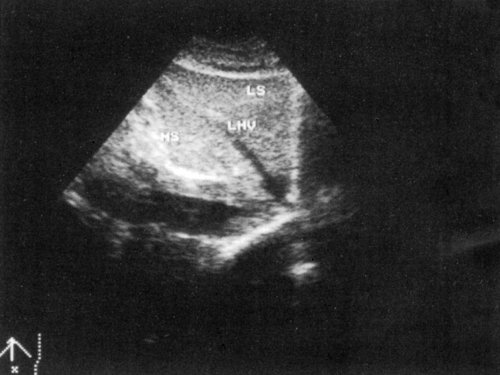

Сегментарное строение печени

Сегментарное строение печени — важная часть ультразвукового исследования, поскольку информация о том, в каком сегменте органа располагается поражение имеет большое значение. Печень может быть разделена печеночными венами следующим образом: правая вена делит правую долю на два сегмента — задний и передний (рис. 10) и левая вена разделяет левую долю на латеральный и медиальный сегменты (рис. 11). Теперь, если мы проведем продольные плоскости через левую, среднюю и правую главные воротные вены (рис. 12), то печень будет разделена на восемь сегментов (рис. 13).

Рис. 11. Медиальный и латеральный сегменты левой доли печени (эхограмма).

RHV — правая печеночная вена, MHV — средняя печеночная вена, LHV — левая печеночная вена, RPV — правая главная воротная вена, LPV — левая главная воротная вена.

Рис. 13. Печень разделена на восемь сегментов следующим образом: 1 — хвостатая доля, которая ограничена сзади нижней полой веной и спереди главной печеночной бороздой; 2 и 3 — левый латеральный сегмент; 4 — левый медиальный сегмент; 5 и 8 — правый передний сегмент; 6 и 7 — правый задний сегмент.